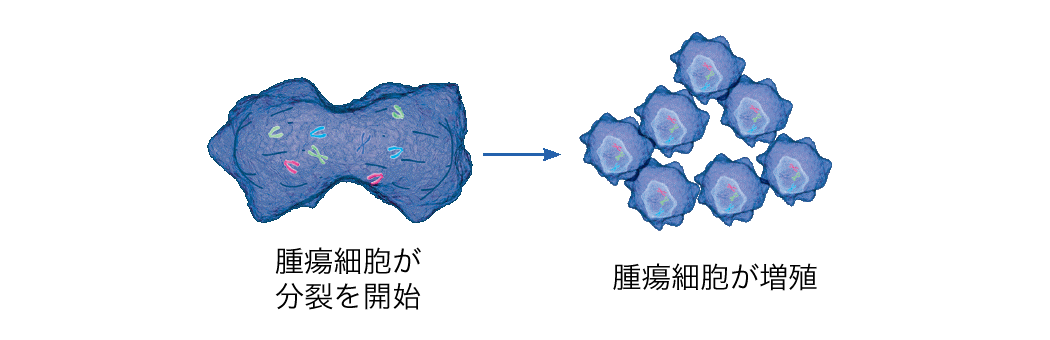

腫瘍治療電場療法のしくみ - オプチューン製品情報サイト,

腫瘍治療電場療法のしくみ - オプチューン製品情報サイト, 他院で取れないと言われた眼窩腫瘍MRIシリーズ④ #orbital tumor,